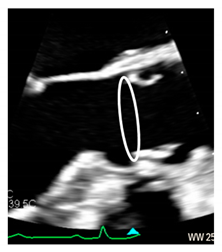

| Virtual or “echocardiographic” annulus | This term refers to a circumference that joins the lowest points of the leaflet insertion. Although neither anatomically or histologically recognizable, this term has become relevant in the TAVI era. Measurements of this virtual basal plane are used for the sizing of the valve in tricuspid valves. This virtual annuls does not have an anatomic counterpart. | ![]() |